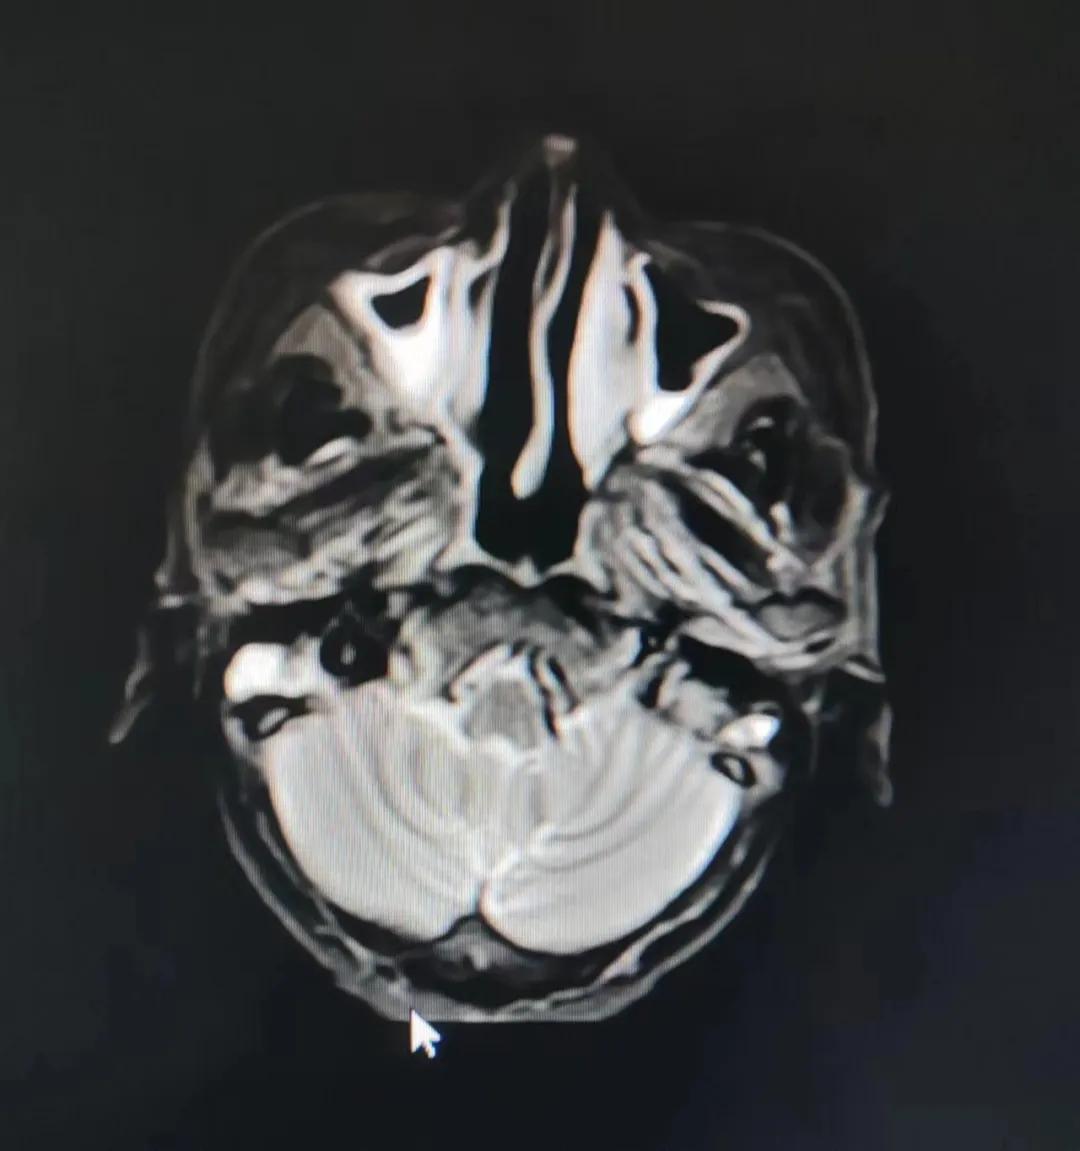

治療前

老人因鼻部腫物堵塞鼻腔并且侵犯鼻咽導致鼻塞、疼痛、吞咽困難,身心都備受煎熬,趙亮主任在詢問其病史期間幾度落淚。趙亮主任向患者及家屬解釋說:“現(xiàn)代放療比過去的傳統(tǒng)放療設備先進,技術不斷提升,能對腫瘤區(qū)域的照射劑量進行優(yōu)化,做到準確定位、精準照射,同時,最大限度地降低正常組織的受量,對全身情況影響很小。”

考慮到患者年齡較大、體質(zhì)差,手術難度大,且常規(guī)的放射治療難以保護患者晶體造成患者雙眼視力損傷,放療團隊以最快的速度制定了精準放射治療方案并開始為其實施治療。僅僅數(shù)日后,老人腫塊出血即得到控制,腫塊明顯縮小,放療20次后腫塊迅速縮小!